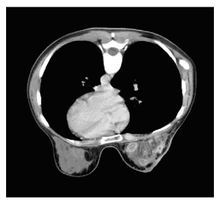

左乳漿細胞性乳腺炎MSCT病灶多在乳暈附近,局部紅腫,疼痛。一般不發燒。過幾天可以自行消退,當勞累、感冒等抵抗力低下時再次發作,但一次比一次重,腫塊逐漸變大,紅腫,一般醫生認為是小膿腫,或用抗菌素打針、輸液,最後切開引流,這樣就形成了瘺管,難以癒合。有時紅腫自行破潰,同樣長久不愈。